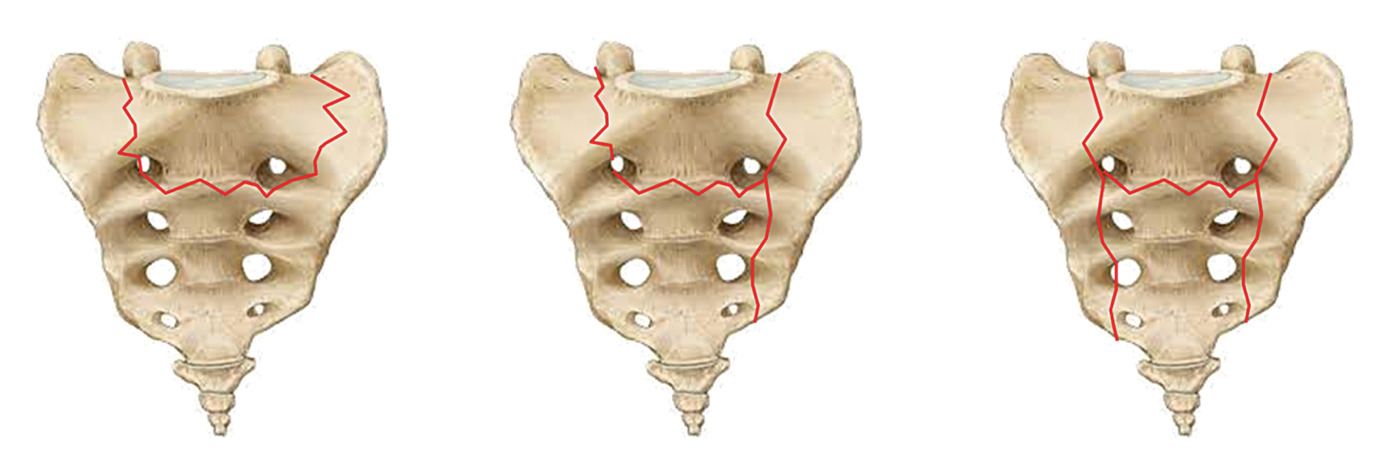

The Rommens43 and OF-Pelvic44 classifications are two pivotal systems for categorizing pelvic fractures, each with distinct focuses and approaches. Together, these classifications provide complementary insights into fracture management, balancing stability-focused categorization with a holistic, score-driven evaluation. Both systems are specifically designed to address fragility fractures.

The Rommens classification emphasizes fracture stability and morphology, categorizing fractures into four main types with increasing instability from type 1 to type 4.43 Type 1 (20% of cases) involves isolated anterior pelvic ring fractures, treated conservatively, while type 4 (20% cases) represents bilateral displaced posterior pelvic ring fractures, the most unstable, often requiring direct surgery. Type 2, the most common (50% of cases), includes non-displaced posterior fractures and may need surgery if pain or mobilization issues persist, while type 3 (10% of cases) involves unilateral displaced posterior fractures.43

Notably, up to 80% of these fractures may require surgical intervention.45 Unlike classifications for non-fragility fractures, which prioritize mechanical forces and trauma mechanisms, the Rommens system focuses on the unique challenges posed by weakened bone structures. However, it does not predict clinical outcomes. Instead, treatment success is defined by pain reduction and early mobilization, emphasizing the need to tailor treatment plans to individual patient needs rather than relying solely on classification systems. Surgical success is measured by reduced pain, improved mobility and enhanced quality of life. For younger patients, more aggressive treatments may be necessary to maintain alignment and mobility, while for elderly patients, the focus is often on pain relief and improving quality of life.